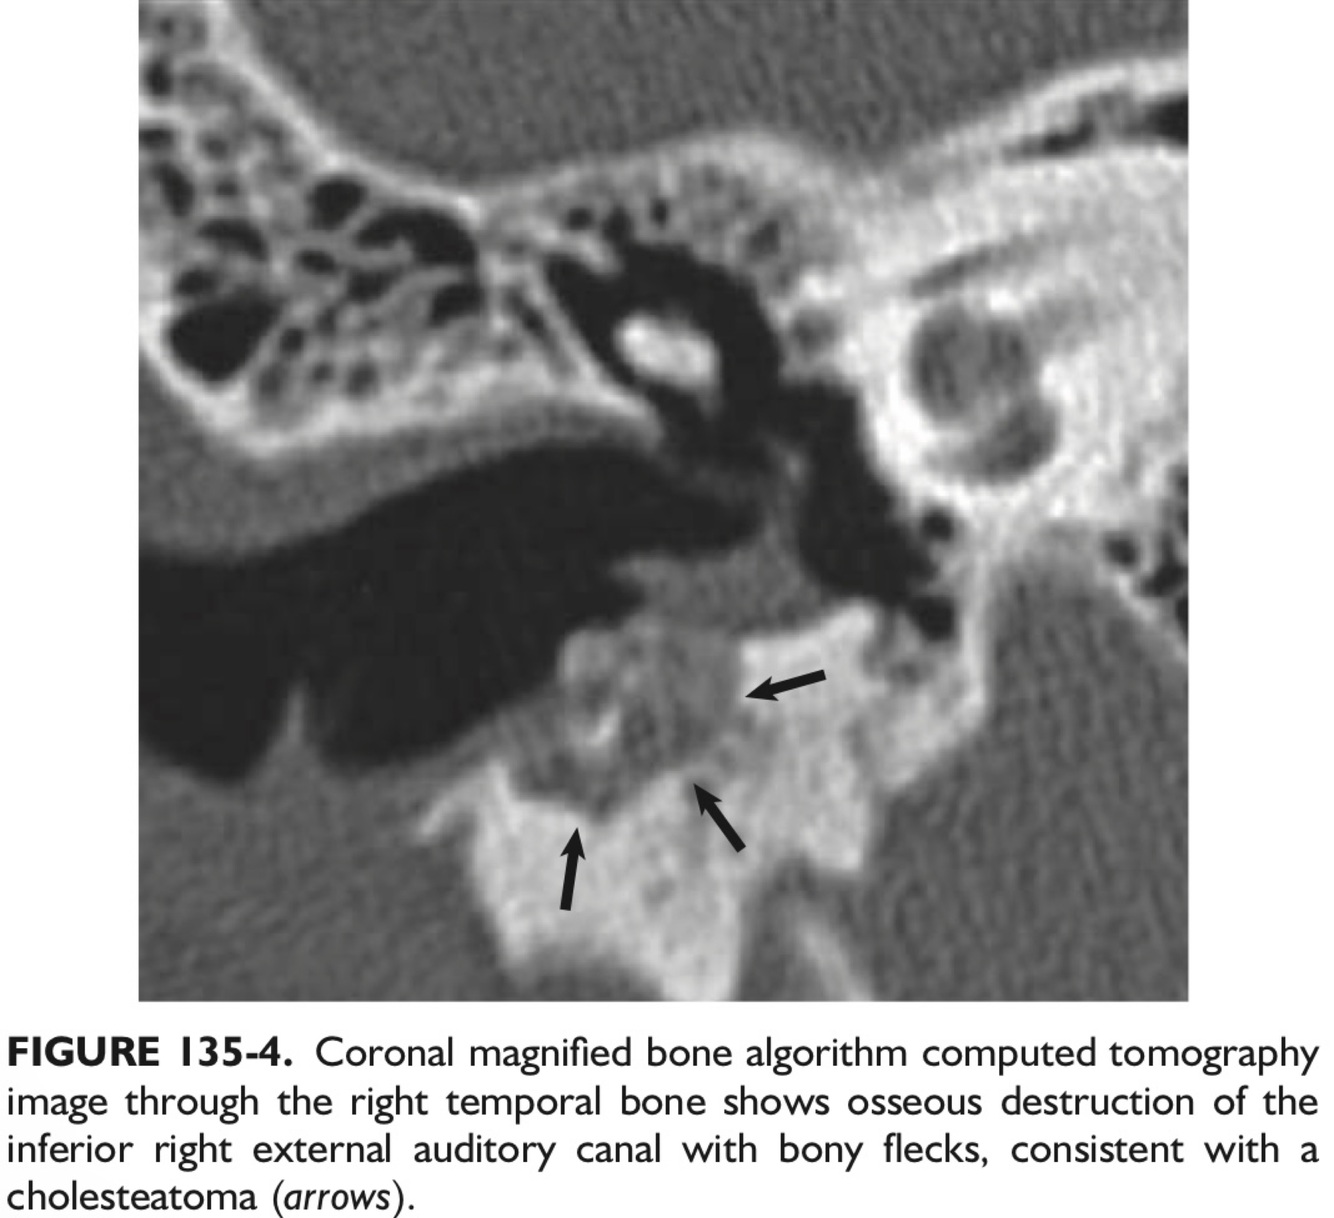

Q

The hallmark imaging finding of cholesteatoma, regardless of location, is ___.

A

Bony Erosion.

Likely diagnosis?

The typical imaging finding associated w/EAC cholesteatoma is a homogeneous, erosive soft tissue mass in the inferior and posterior EAC, (w/scalloped bone and flecks of bone w/in the lesion in 50% of cases).